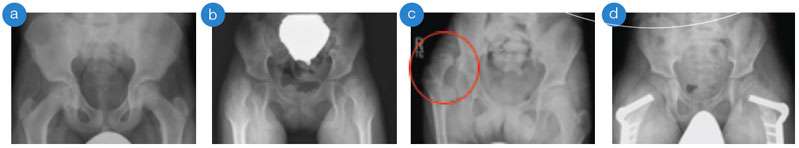

(a) normal hips and pelvis, (b) subluxated/partially dislocated hips, (c) right dislocated hip (circle), (d) after surgical correction of subluxated hips with plates and screws

Typically, certain muscles are more spastic than others. This muscle imbalance, combined with delayed weight bearing, may lead to hip dislocation, when the top of the femur (thigh bone), moves out of the hip socket. Hip dislocation in children with cerebral palsy is associat­ed with difficulties in sitting, personal care and hygiene and pain or scoliosis (curvature of the spine) may occur. The team at the UCLA/LOIC CCP is committed to preventing hip dislocations in children with cerebral palsy by performing regular exams and obtaining x-rays over time. This is called hip surveillance. Our method of hip surveillance is based on evidence and best practice from clinicians around the world.

• Surgical release of spastic muscles for “hips at risk” – hips that are partially dislocated, or “subluxated”, to prevent full dislocation

• Surgery of the hip and pelvic bones for more severely affected hips (those with a greater amount of subluxation) in older children